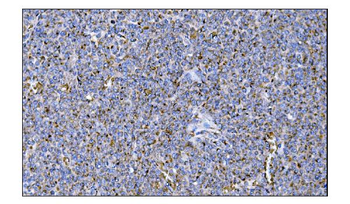

IHC staining of FFPE human colon carcinoma with MerTK antibody (clone TPKR-1). HIER: boil tissue sections in pH9 10mM Tris with 1mM EDTA for 10-20 min and allow to cool before testing.